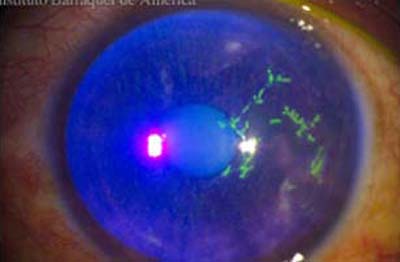

La forma más frecuente de la queratitis herpética es la ulcera dendrítica, que es una lesión lineal ramificada con bulbos terminales y bordes inflamados que contienen virus vivos. Se tiñe positivamente con fluoresceina lo que facilita su diagnóstico; compromete el epitelio pudiendo alcanzar la membrana basal en la etapa inicial. Produce sensación de cuerpo extraño, lagrimeo y visión borrosa.

Cuando la úlcera pierde su caracter lineal, se la conoce como “ ulcera geográfica” que representa a una lesión dendrítica extendida y se asocian a una mayor duración de los síntomas y con frecuencia al uso previo de corticoides.

Herpes Simple

Herpes Simple